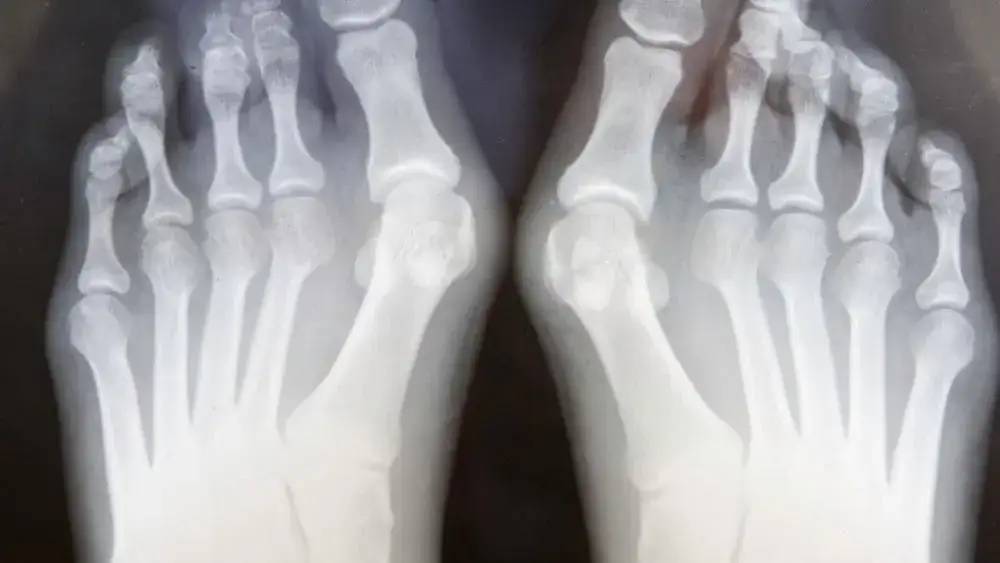

Ortopeda to najlepszy specjalista, do którego warto się udać w przypadku haluksów. Posiada on odpowiednie kwalifikacje oraz umiejętności, aby skutecznie ocenić stan stóp pacjenta. Ortopeda przeprowadza kompleksową diagnostykę, w tym zleca badania obrazowe, takie jak zdjęcia RTG, co pozwala na dokładną ocenę deformacji.

W trakcie wizyty ortopeda może zlecić różne badania diagnostyczne, aby dokładnie ocenić stan zdrowia stóp. Najczęściej wykonywane badania to zdjęcia RTG, które pozwalają zobaczyć stopień deformacji oraz ocenić, jak zmiany wpływają na układ kostno-stawowy. W niektórych przypadkach lekarz może również przeprowadzić badanie fizykalne, aby sprawdzić zakres ruchu w stawach oraz zidentyfikować miejsca bólu.

- RTG stopy – badanie obrazowe, które pozwala ocenić stopień zaawansowania deformacji oraz stan kości.